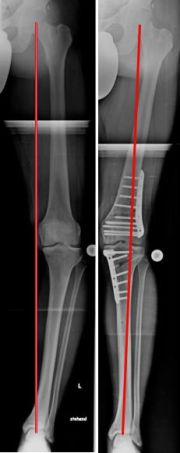

Beispiel einer aufklappenden Osteotomie, kniegelenksnah, am Schienbein bei O-Beinfehlstellung. Die MA wurde zentriert, da noch keine Schädigung des Gelenkes vorlag (Bild 2).